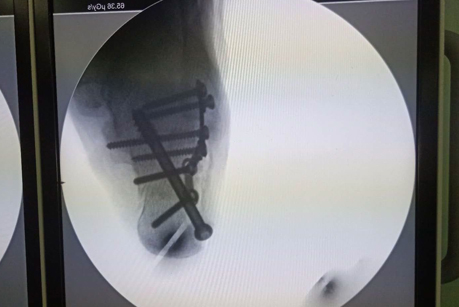

术中X线片可见骨折几乎解剖复位